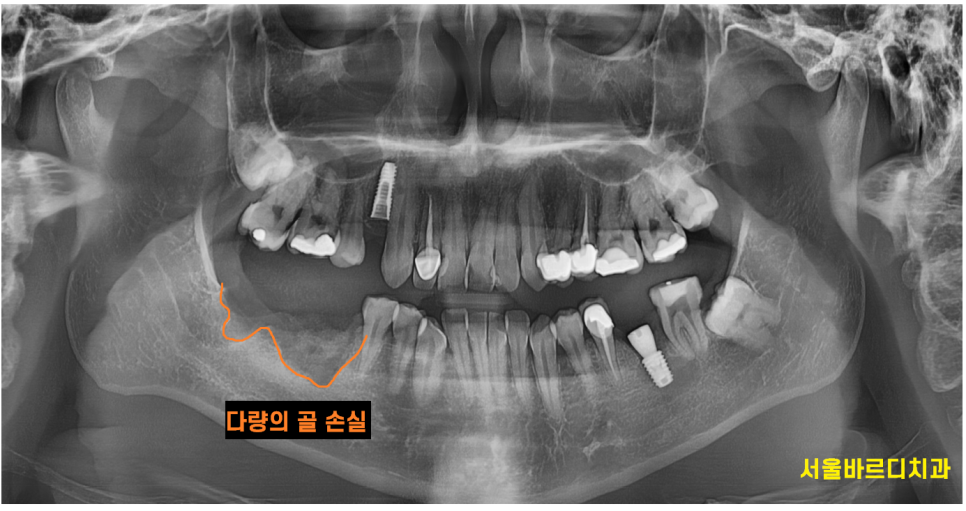

(1) 환자의 구강 건강 상태

아무래도 임플란트를 잇몸 뼈에 식립하다보니

충분한 뼈의 양과 질이 중요해요~

너무 염증 상태를 방치하면 잇몸뼈가 부족하게되고

많은 양의 뼈이식을 해주어야하는데요.

어떤 경우에는 두번씩 뼈를 이식하기도 합니다.

241127

문제는 뼈이식을 많이해도 이식한 양만큼 뼈가 만들어지는게 아니고

뼈이식을 많이할수록 상태가 안좋았다는 것이기에

임플란트가 제대로 자리잡지 못할 가능성이 높아집니다!